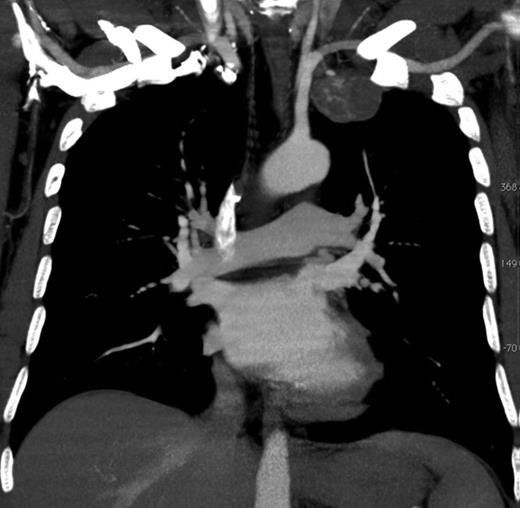

However, chest X-ray should be performed as first step when IMAA is suspected. An additional CT scan conceivably in combination with an angiography is a valuable method to localize the IMAA and to plan the surgical procedure [1]. In our patient, classical symptoms of an IMAA were missing and the IMAA was an incidental finding within routine X-ray. The compression symptoms of the IMAA were only found after accurate request and examination. The additional imaging procedures failed to confirm the diagnosis.